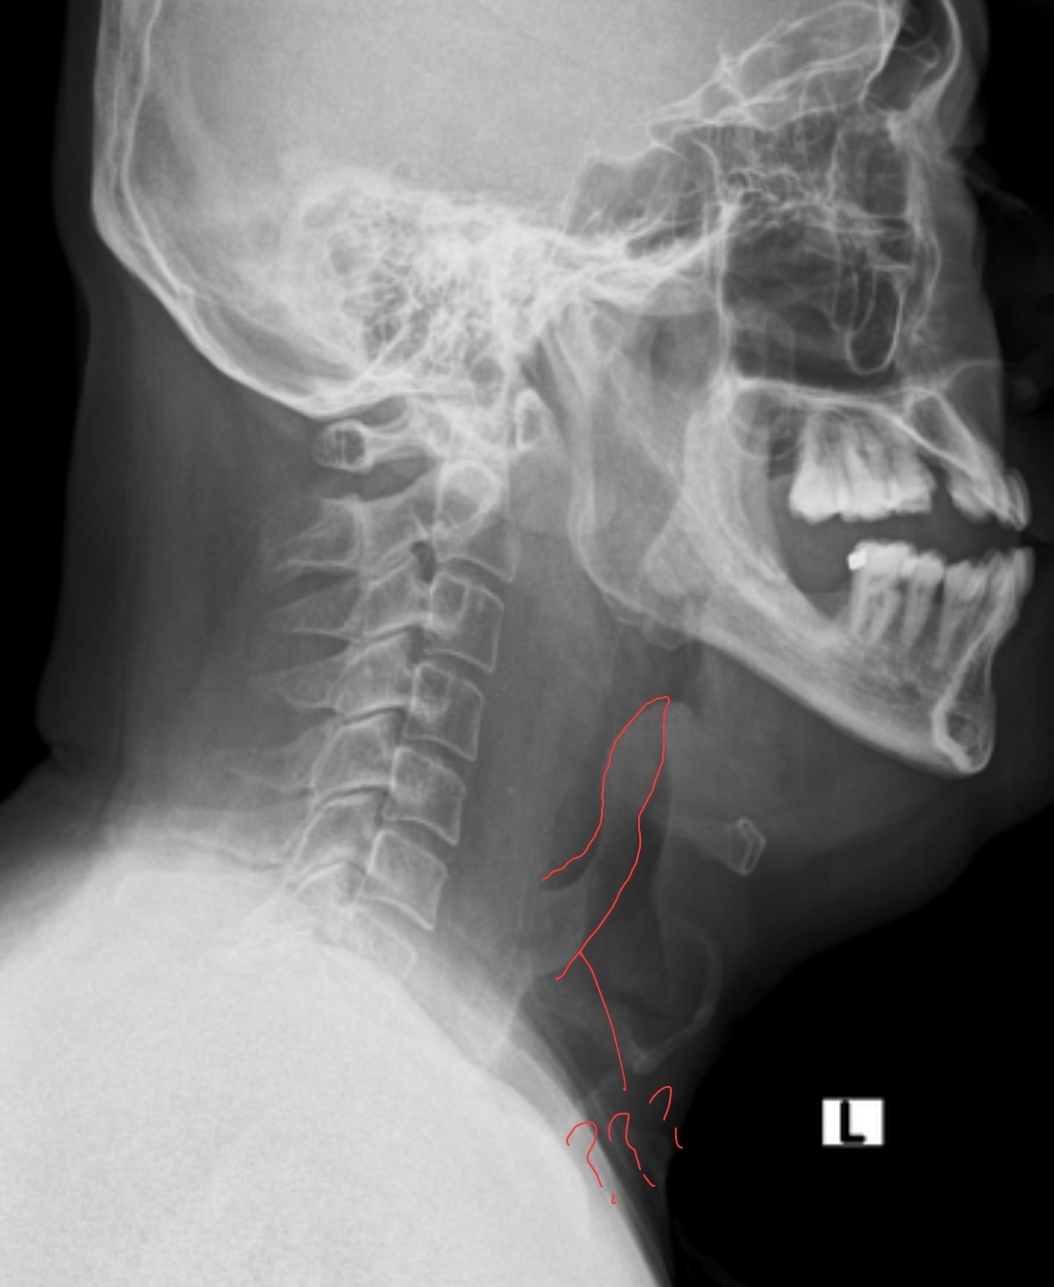

이 튀어나온 구조물은 무엇인가요 - 2025년 전공의시험 1회 91번 | 메디톡

image size: 1054x1287

유익한 정보네요. 엑스레이에서 안보이면 CT를 찍죠? 생선가시도 뼈라서, CT에서 뾰족한 하얀 뼈가 잘 보인답니다. 그리고 가시 때문에 식도 천공, 위 천공되서 응급수술 받고 중환자실 신세 지는 분들도 꽤 많으니 생선가시는 꼭꼭 씹어드시지

image size: 1600x897